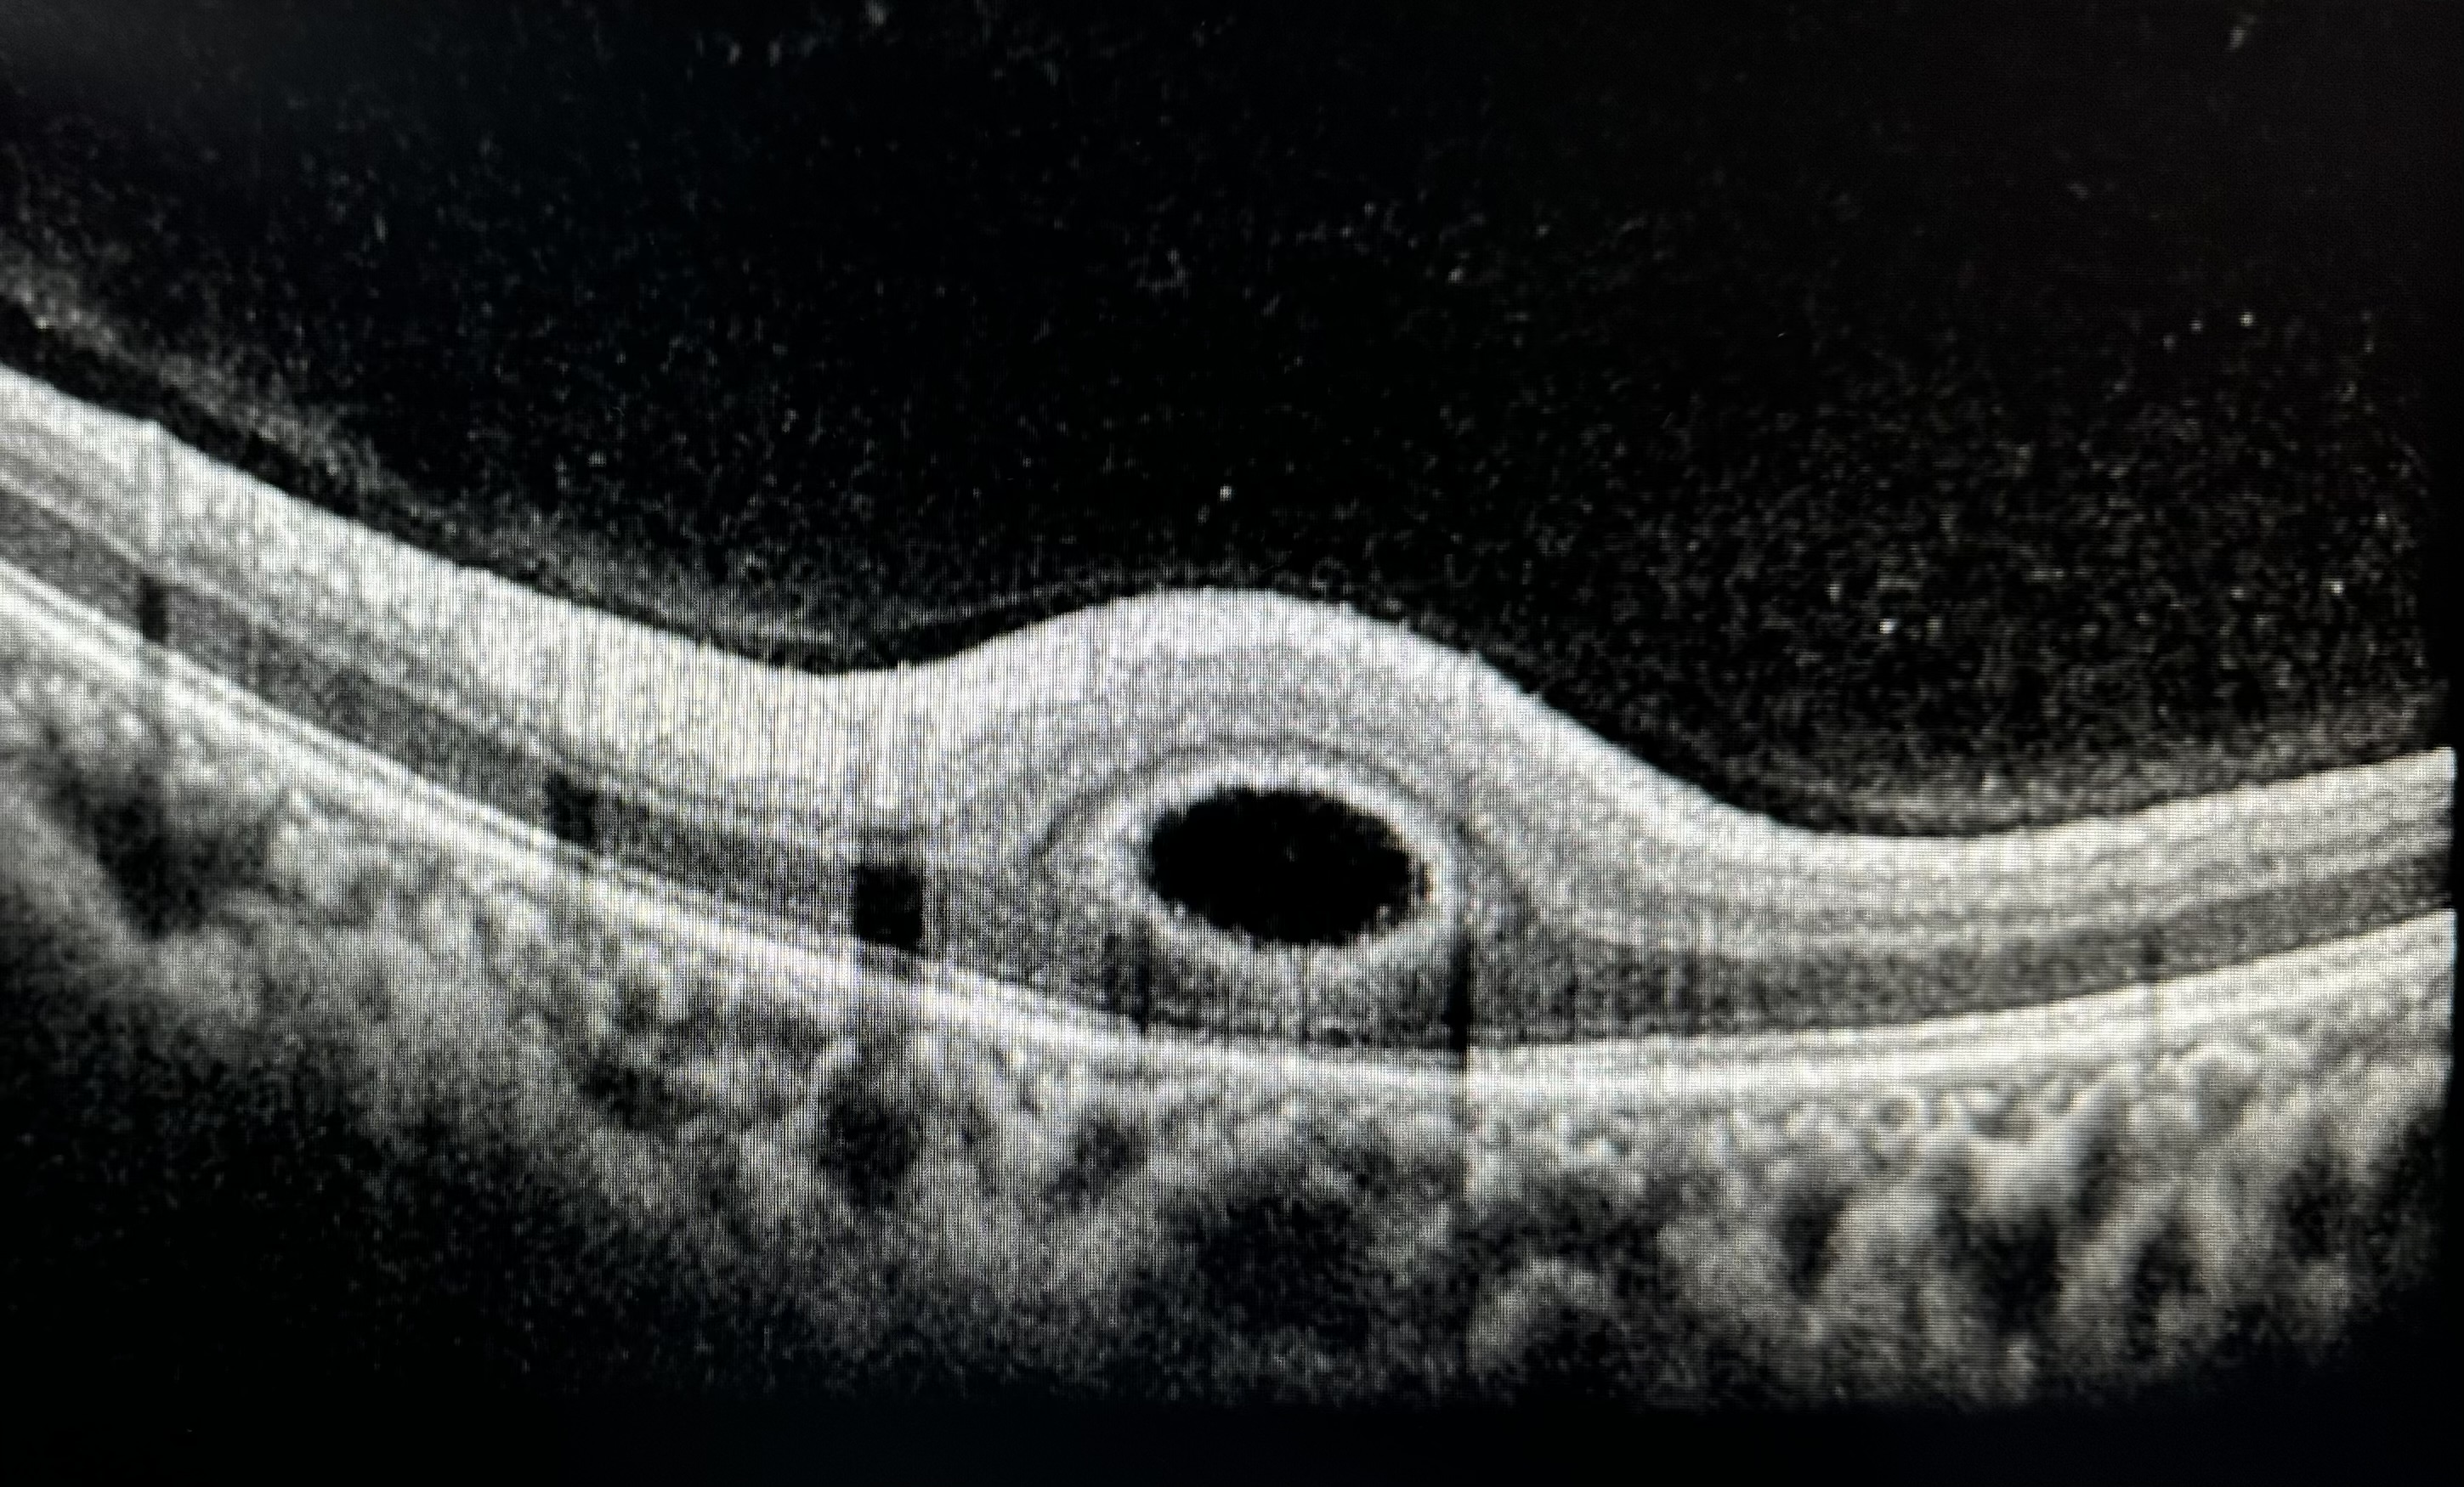

Title: “Retina Buttonholed”

Description: It’s an OCT depicting one of the patterns of intraretinal fluid progression in a case of Optic disc pit. 21 years old girl diagnosed as ‘Karnenburg syndrome bei grubenpapille’ in Germany presented to us for surgical intervention, as already advised there. Examination at presentation, revealed optic disc pit with retinoschisis, intraretinal and subretinal fluid(SRF) with SRF being the predominant fluid type. SRF, surprisingly showed very fast progression to more than 1600 microns from 1049 microns accompanied with painless drop of VA from 6/60 to 3/60 over two weeks. Fundus fluorescein angiography performed to rule out other possibilities. The scan has been taken at the edge of fast progressing fluid over two weeks , and observes one of the ways of fluid progression in Optic disc pit that leads to schisis prior to SRF being captured as a ‘Button hole’ appearance.